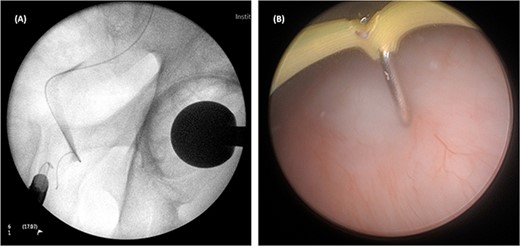

On both cases, under general or regional anaesthesia, a cystoscopy was performed and the interureteric bar was identified. A hybrid ‘sensor’ or ‘Terumo’ hydrophilic guidewire was advanced concurrently using the access from the existing nephrostomy tube with fluoroscopic assistance down to the level of the ureteric cul-de-sac. A combined visual- and x-ray-guided approach verified the exact location of the course of the intramural ureter, in correlation to the resectoscope and a Collins knife was used to incise the bladder mucosa (Fig. 2) above the level of the guidewire, on the virtual course of the intramural ureter exposing the intramural ureter. In all three attempts, the incision of bladder mucosa above the antegrade ureteric guidewire ended up with a successful identification of the guidewire, allowing access to the ureteric cul-de-sac. Stent graspers were used to snare the guidewire into the bladder (Fig. 3). With safety wire in place, management of the neo-orifice could then be performed.

Cystoscopic view of exposed left VUJ with identification of terumo guidewire passed antegradely.